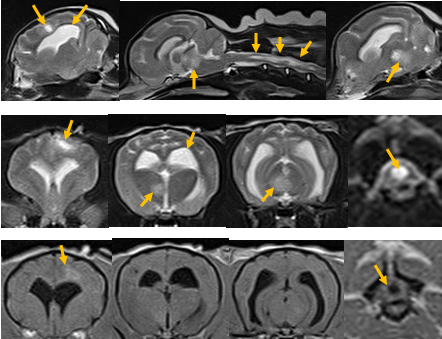

进行血液常规检查,评价狗狗基础身体状态,是否存在严重的感染。进行脑部CT或者核磁的检查,确诊脑部结构有无异常。狗狗患脑膜炎,可能会出现兴奋、体温升高、不安、抽搐、肌肉痉挛、乱叫、食欲不振、没有目的的狂跑等症状。一般引起狗狗脑膜炎的原因,包括感染细菌、病毒、寄生虫及外部损伤等。